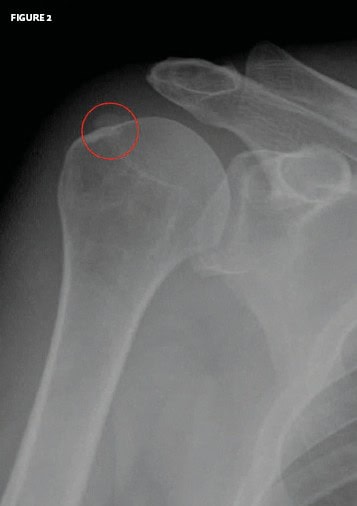

The x-ray shows calcification along the head of the humerus, which is consistent with a calcific tendinitis.

This patient was advised to follow up with an orthopedist. One might also consider a local cortisone injection, with or without physical therapy, in such a case.